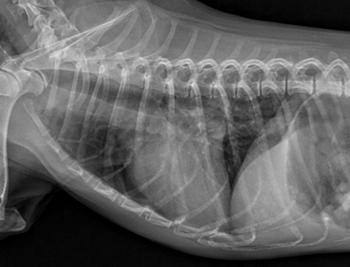

일주일 후 내원한 아이는 식욕도 많이 좋아지고 호흡도 좋아졌습니다. 방사선과 초음파입니다.

방사선상 유의미하게 심장 크기가 줄어들고 폐부종은 모두 사라졌습니다!